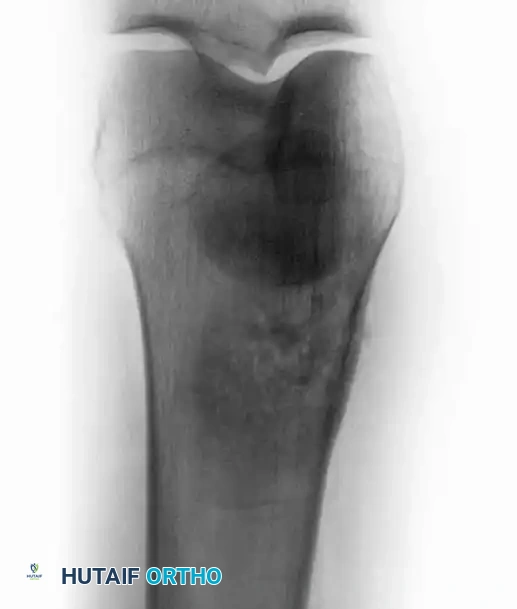

Intraoperative Imaging and Margin Assessment

Continuous intraoperative assessment using fluoroscopy and frozen section pathology is mandatory. The following images demonstrate various stages of complex upper extremity resections, allograft preparations, and prosthetic implantations across the humerus and elbow joint.

Advanced Reconstructive Modalities and Distal Extensions

While proximal humeral resections dominate shoulder oncology, tumors extending into the humeral diaphysis or distal humerus require equally complex limb salvage strategies. Total humeral replacement or distal humeral megaprostheses are viable options when the radial nerve can be preserved or grafted.